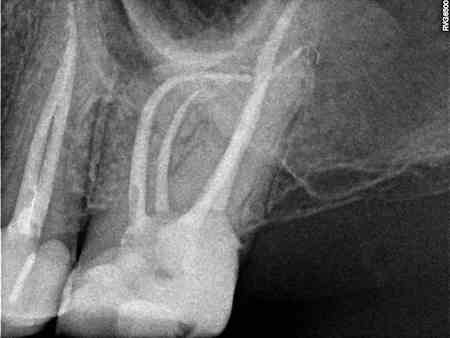

De endodontie of wortelkanaalbehandeling bestaat uit het verwijderen van zenuwen die zich in de wortels van de tanden bevinden. Na het verwijderen zal de tand weer opgevuld worden. Deze behandeling zal u weer een comfortabel gevoel geven.